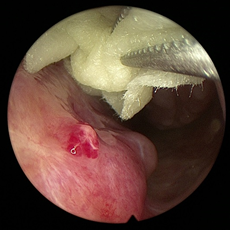

鼻腔内多量脓性分泌物,鼻甲完整,粘膜充血红肿,如图5及图6所示